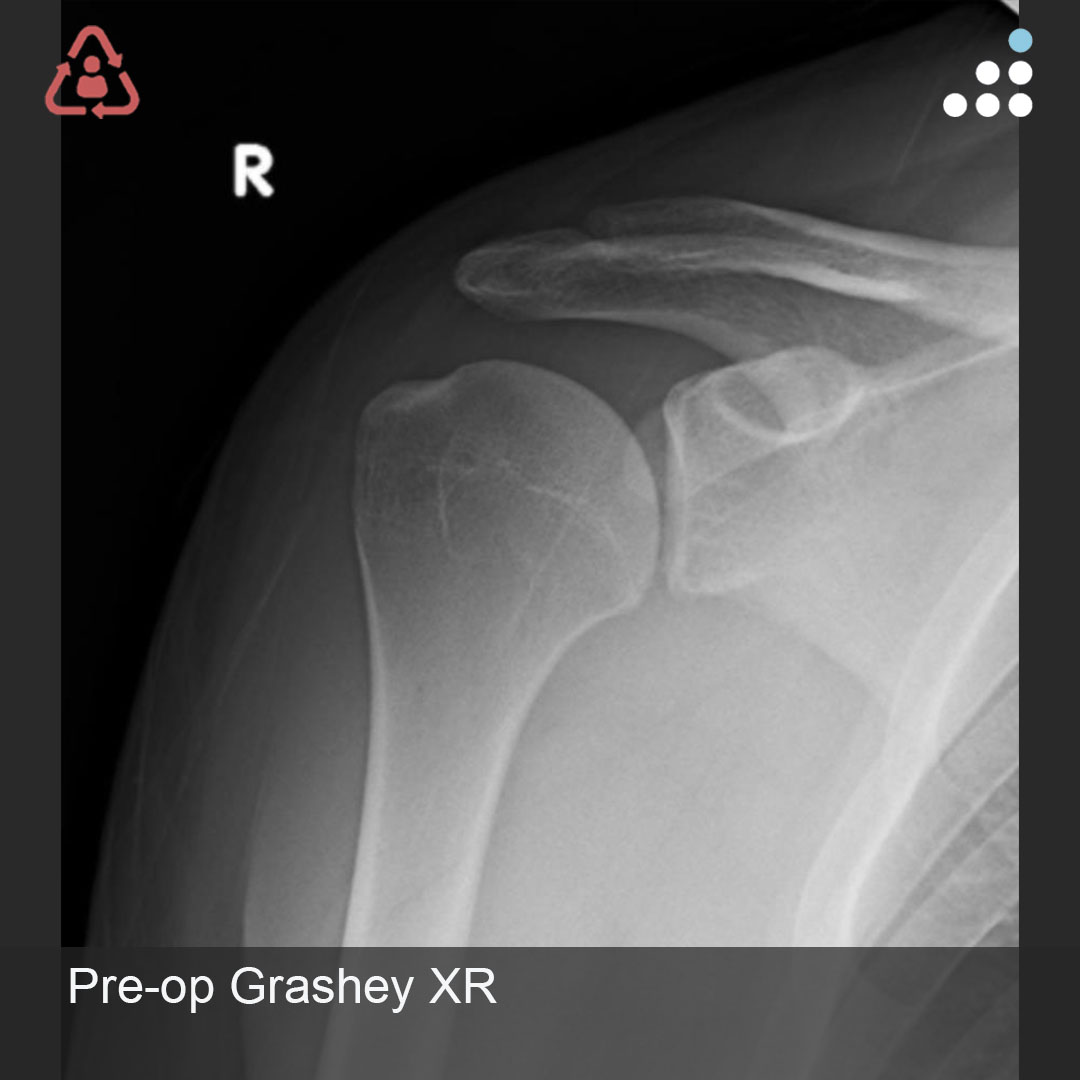

@DrBryanSaltzman @orthotraumamd @orthobullets @VaniSabesanMD @JSanchezSotelo @RachelFrankMD @MarkFrankleMD @shoulderMD I agree with Dr Saltzman. This is a preservable joint in a young active individual. Tuberoplasty or spacer would be my choice.